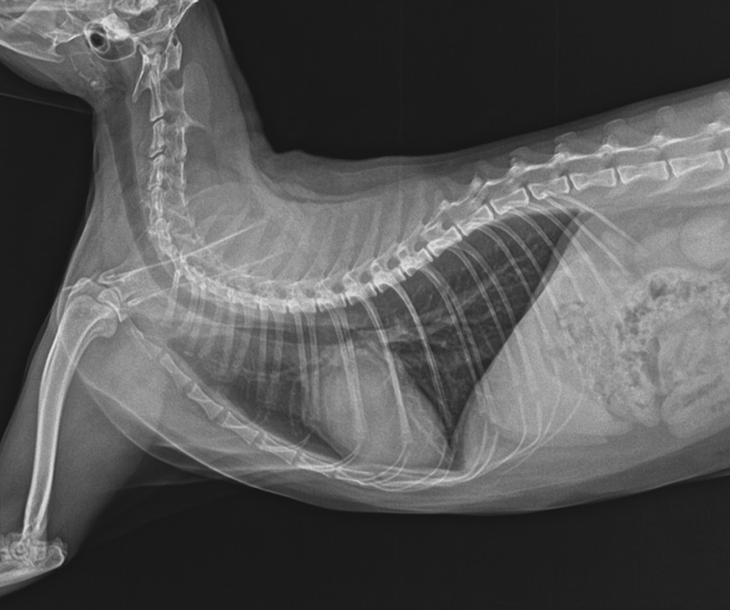

비대성 심근증

고양이에서 가장 흔한 심장 질환은 심근비대증입니다. 이 질환은 심장 근육이 두꺼워지면서 심실 내부 공간이 좁아지고, 이에 따라 전신에 보내는 혈액의 양이 감소하여 순환 장애가 발생하는 상황을 말합니다. 대개 선천적인 원인이지만 고혈압,갑상선 기능 항진증,스테로이드등 다양한 요인에 의해 발생할 수 있습니다. 이에 따라 정기적인 검진이 필수적입니다.